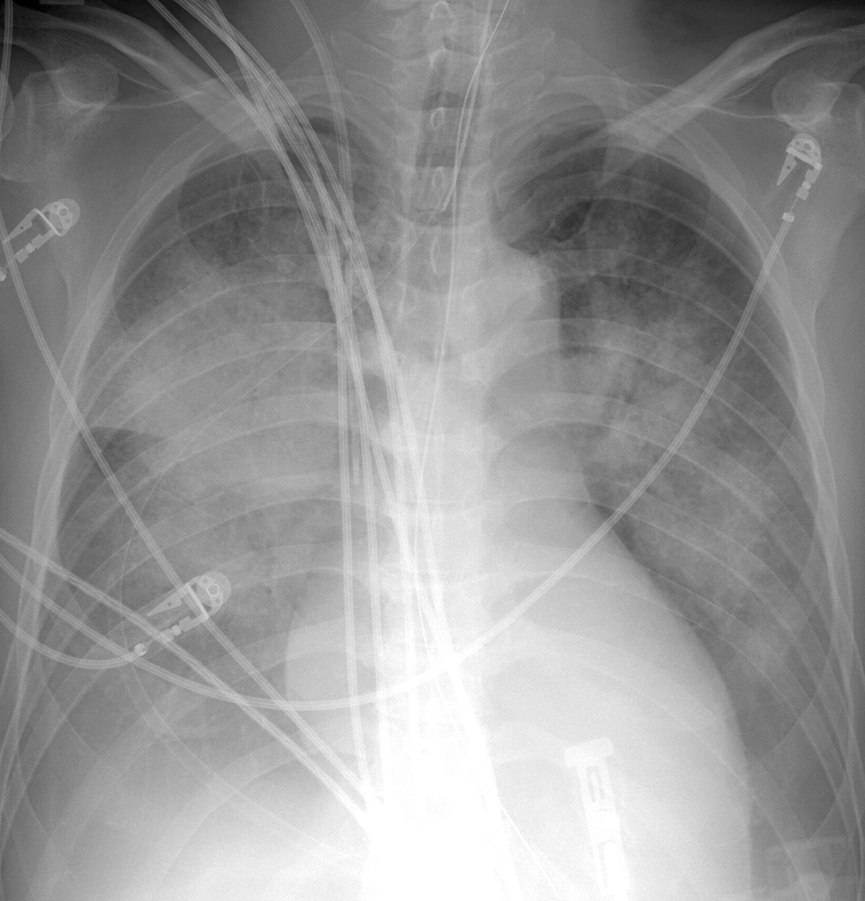

Gallery Cardiac Heart failure APE 1

APE 1